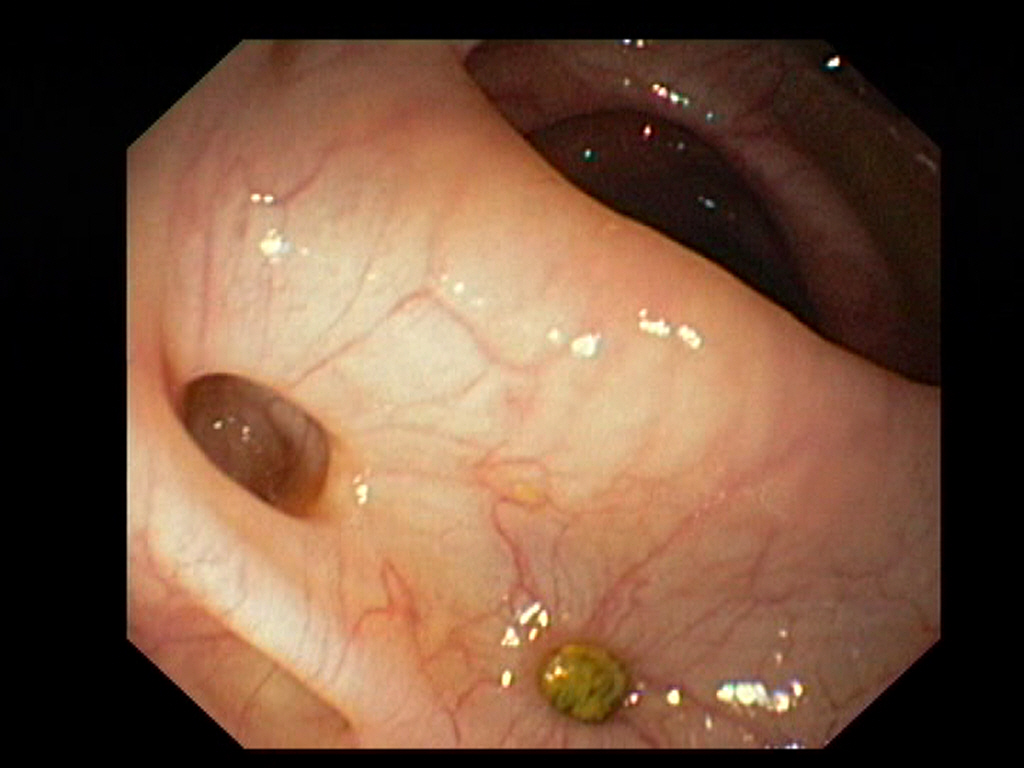

Diverticulosis in the Sigmoid Colon

Diverticulosis in the Sigmoid ColonJust click on a picture!